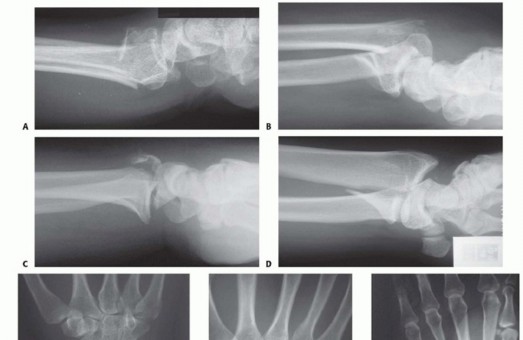

FIG 3 • Pathogenesis of dorsal radius fractures. A. Dorsal bending. B. Volar bending. C. Dorsal shear. D. Volar shear. E. Radial shear. F. Three-part articular. G. Comminuted articular. H. Carpal avulsion. I. High energy.